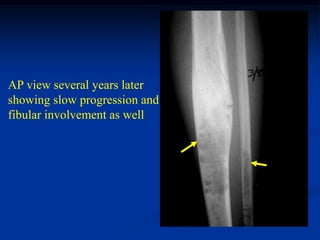

Case #1094

15 year female with

adamantinoma arising

from osteofibrous dysplasia

AP view several years later

showing slow progression and

fibular involvement as well